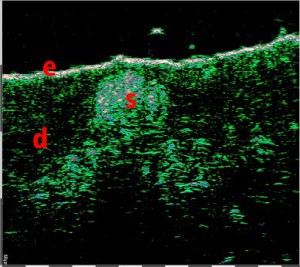

-Έγχυση Πληρωτικών Υλικών (Fillers)